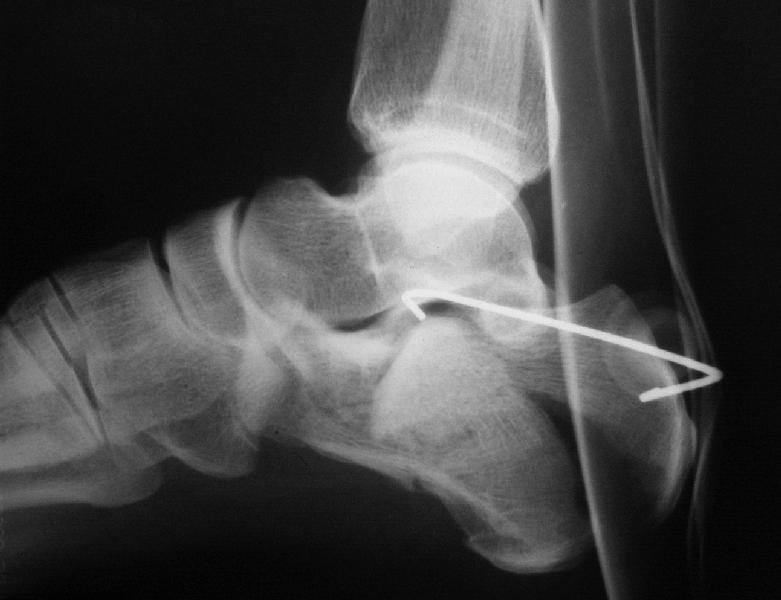

В/суставные переломы пяточной кости у молодых являются показанием к оперативной коррекции, Большой материал накоплен у д-ра Дрягина (Челябинск). В нашем отделении предпочтение отдаем открытой репозиции, при наличии выраженного отека, фликтен и т.д.

Накладываем спицевой дистрактор, позволяющий выхаживать м/ткани и одновременно устранять захождение отломков.

Окончательная фиксация спицами, пяточными пластинами (5) , в последнее время стали применять крючковидные пластины (ДЕОСТ) (6,6a).

Кроме стандартных снимков, необходим контроль конгруэнтности суставной поверхности (проекции Бродена)